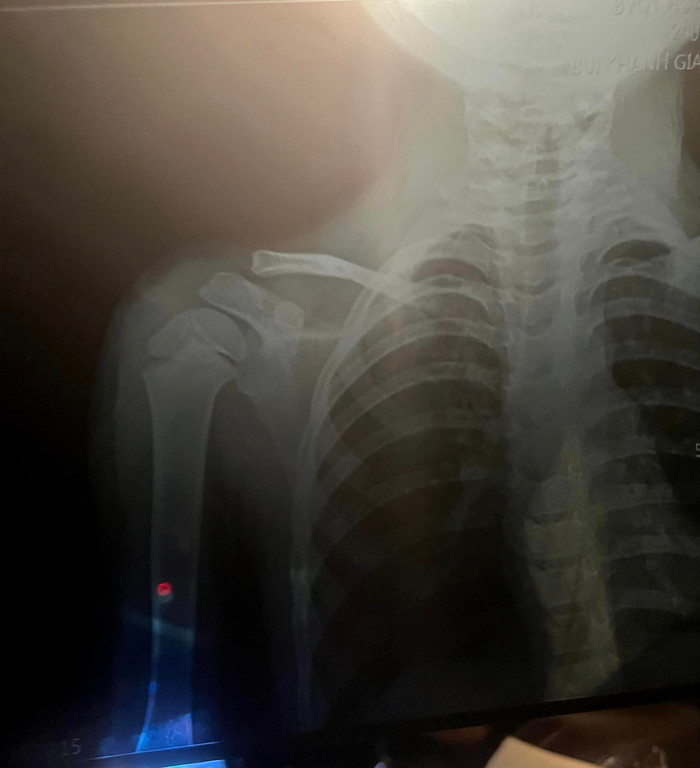

Tối ngày 23/8, Khánh Linh - bà xã cầu thủ Bùi Tiến Dũng chia sẻ hình ảnh con gái là bé Mochi bật khóc nức nở, đang đeo băng để cố định tay trong bệnh viện. Bên cạnh đó, cô còn đăng tải ảnh chụp X-quang con gái bị gãy xương.

Hình ảnh chụp X-quang của con gái được bà xã Bùi Tiến Dũng chia sẻ.